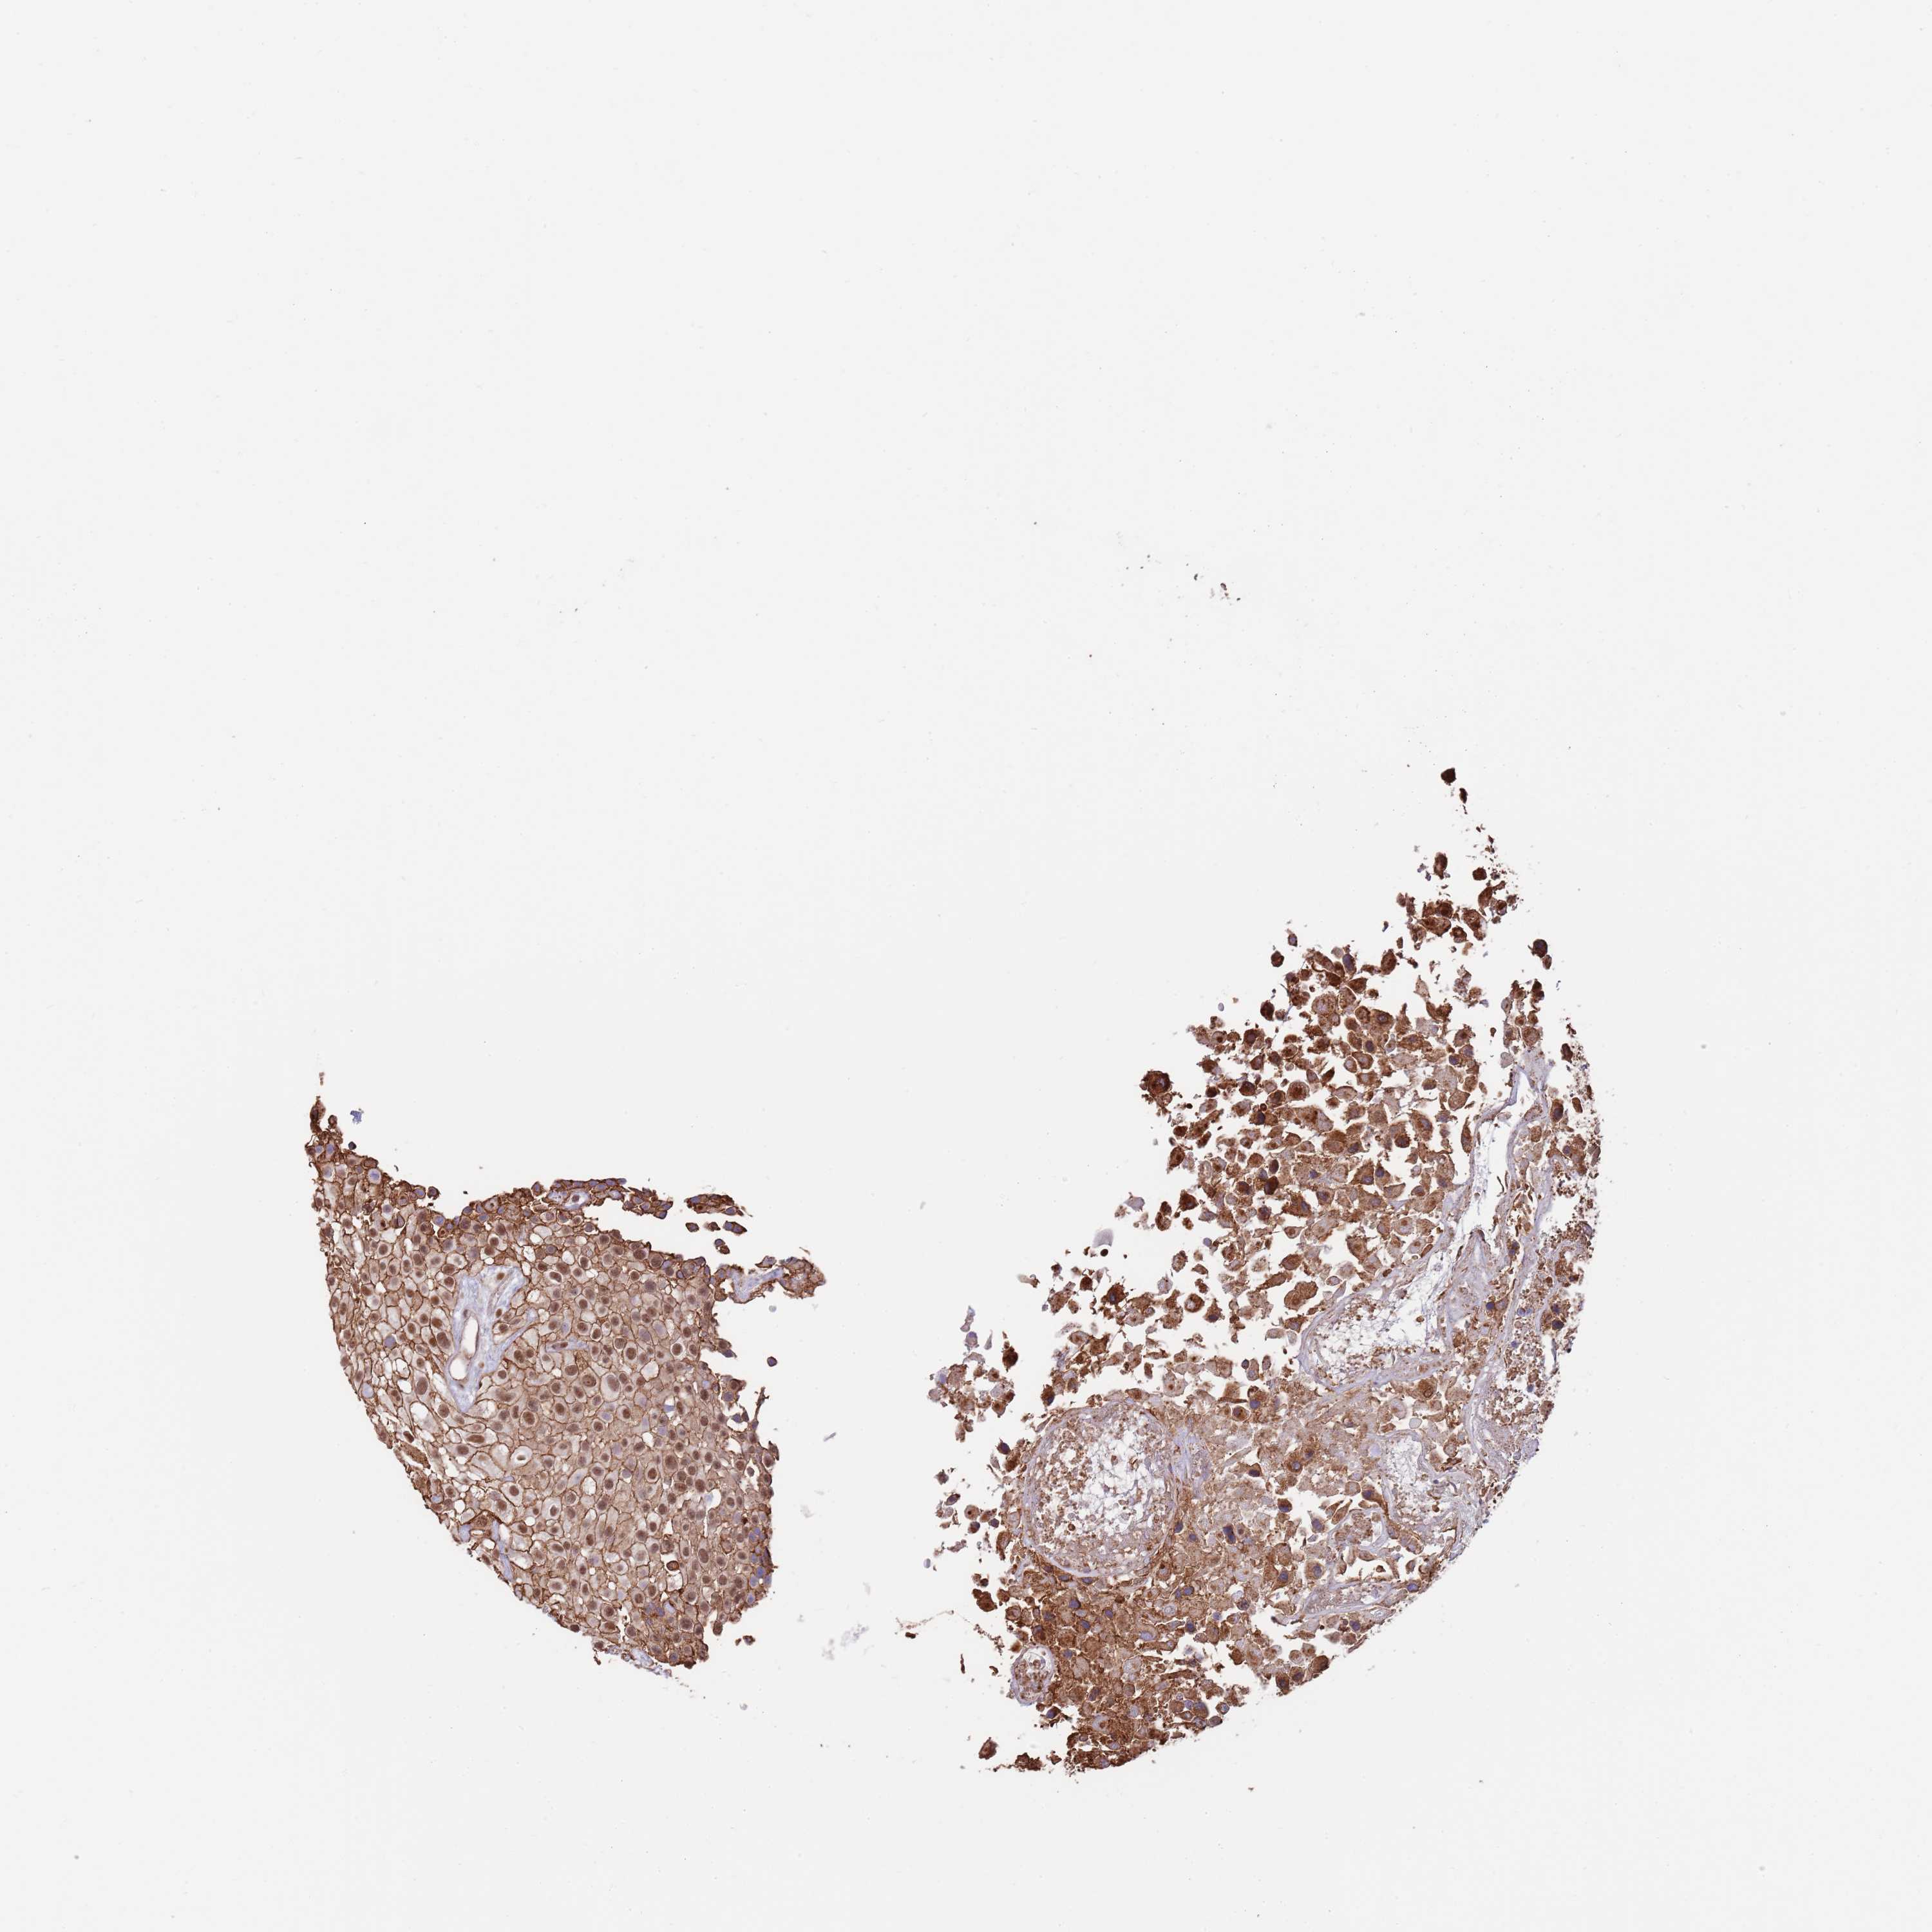

UROTHELIAL CANCER - Protein expressioni

A mouse-over function shows sample information and annotation data. Click on an image to view it in a full screen mode. Samples can be filtered based on level of antibody staining by selecting one or several of the following categories: high, medium, low and not detected. The assay and annotation is described here.

Note that samples used for immunohistochemistry by the Human Protein Atlas do not correspond to samples in the TCGA dataset.

Antibody stainingi

Antibody staining in the annotated cell types in the current human tissue is reported as not detected, low, medium, or high, based on conventional immunohistochemistry profiling in selected tissues. This score is based on the combination of the staining intensity and fraction of stained cells.

Each image is clickable and will lead to virtual microscopy that enables deeper exploration of all samples and also displays staining intensity scores, fraction scores and subcellular localization as well as patient and tissue information for each sample.

Antibody HPA048461

Staining

High

Medium

Low

Not detected

Intensity

Strong

Moderate

Weak

Negative

Quantity

>75%

75%-25%

<25%

None

Location

Nuclear

Cytoplasmic/membranous

Cytoplasmic/membranous,nuclear

Urothelial carcinoma, Low grade

Urothelial carcinoma, High grade

Urothelial carcinoma, NOS